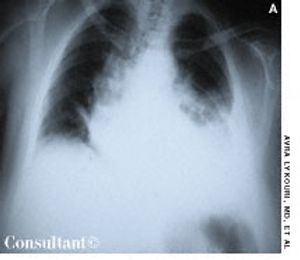

A 65-year-old woman experienced dyspnea, dizziness, and left pleuritic pain several hours after falling down a flight of stairs. Shallow breathing and increased tenderness of the left thoracic wall were evident with palpation. Decreased breath sounds on the left and dullness on percussion were also noted.